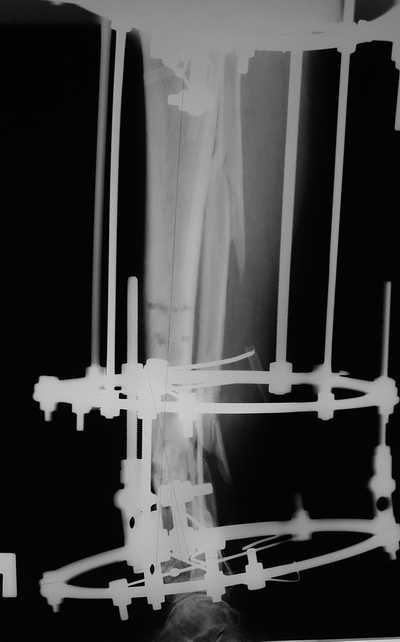

остеотомия м\б кости, аппарат Илизарова. По рентгенограммам в двух проекциях произведено планирование устранения смещений (рис 2 и 3), между вторым и третьим кольцом установлены 6 телескопических дистракторов Гесапода, данные введены в программу, и далее втечение 10 дней больная подкручивала телескопы согласно выданной компьютером инструкции. По завершению репозиции гексаподные телескопы обратно заменены на обычные штанги от аппарата Илизарова (рис 4 и 5). Еще через две недели забит гвоздь (рис 6, контроль

через 4 месяца).